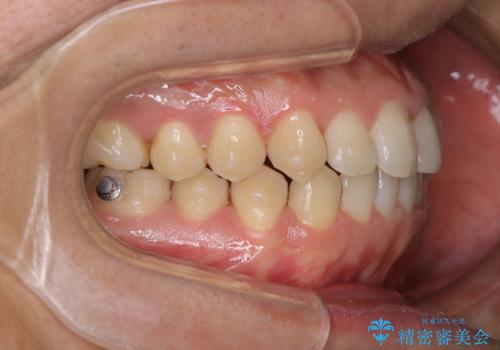

コーヒーを多く飲むインビザライン矯正中の患者様のクリーニング

60分コースでも足りないくらいの着色の量でした。

定期的にクリーニングに来られてますが、かなりの量のコーヒーを飲まれているため着色が多かったです。